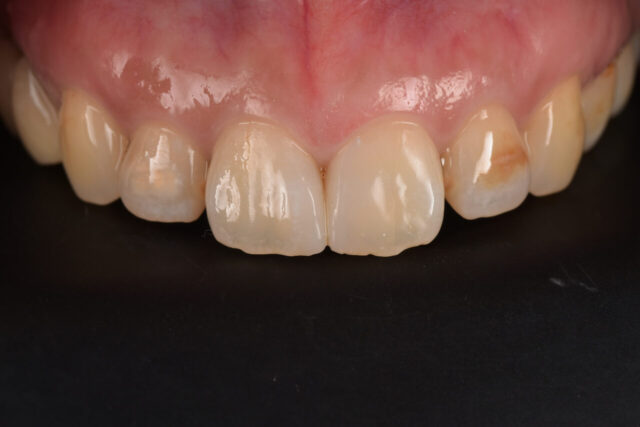

前歯の変色を削らずに改善|ホワイトニング+ダイレクトボンディング症例

before

after

性別 女性 主訴 「前歯の色が気になる」「できれば削らずにきれいにしたい」というご相談で来院されました。 治療 診査の結果、前歯には失活歯による内部からの変色(いわゆる黒ずみ)が認められました。

通常であれば、ラミネートベニアやセラミッククラウンによる修復が検討されるケースです。

しかし本症例では、歯質の保存を最優先に考え、以下の治療を選択しました。

インターナルブリーチ(ウォーキングブリーチ)による内部漂白

色調改善後にダイレクトボンディングによる形態・色調修正

まず歯の内部に漂白剤を作用させることで、歯質自体の明度を改善。

その後、周囲の歯との色調バランスを考慮しながらコンポジットレジンにて微調整を行いました。

結果として、歯を大きく削ることなく、自然で調和のとれた前歯の審美性を回復することができました。料金 1本10万円+tax 備考 本症例のポイントは、「削らない選択肢」を最大限活かした点にあります。

失活歯の変色に対しては、従来セラミック治療が第一選択とされることも多いですが、

インターナルブリーチを適切に行うことで、歯質を温存したまま審美改善が可能なケースも存在します。

また、ダイレクトボンディングを併用することで、

色調の微調整

透明感の再現

最小限の介入での形態修正

が可能となり、より自然な仕上がりが得られます。